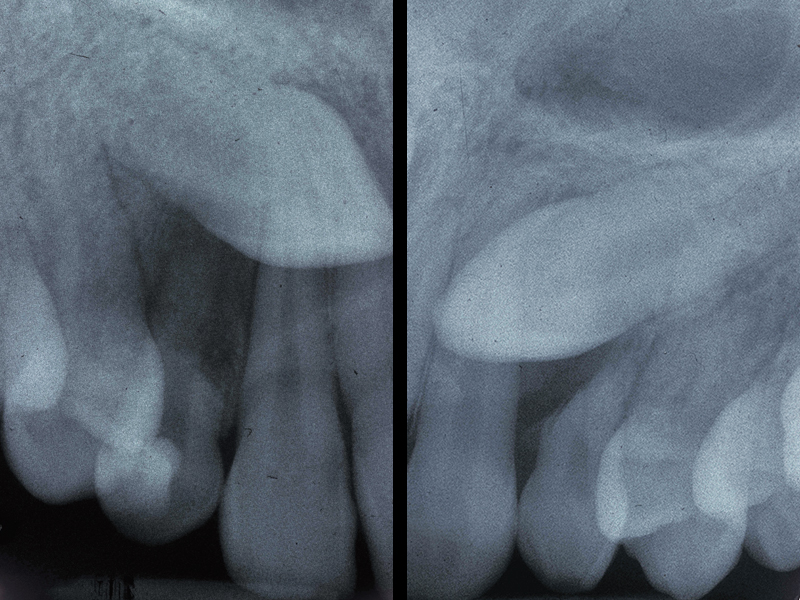

Impacted Teeth:

As children grow, the erupting permanent teeth push out the overlying baby tooth. When permanent teeth fail to come in, they are termed …impacted. This occurs with upper canines as well as other teeth. In these situations, a periodontist may be asked to surgically expose the tooth and attach a chain so that an orthodontist can actively

engage the tooth, assisting it in a successful erupt.